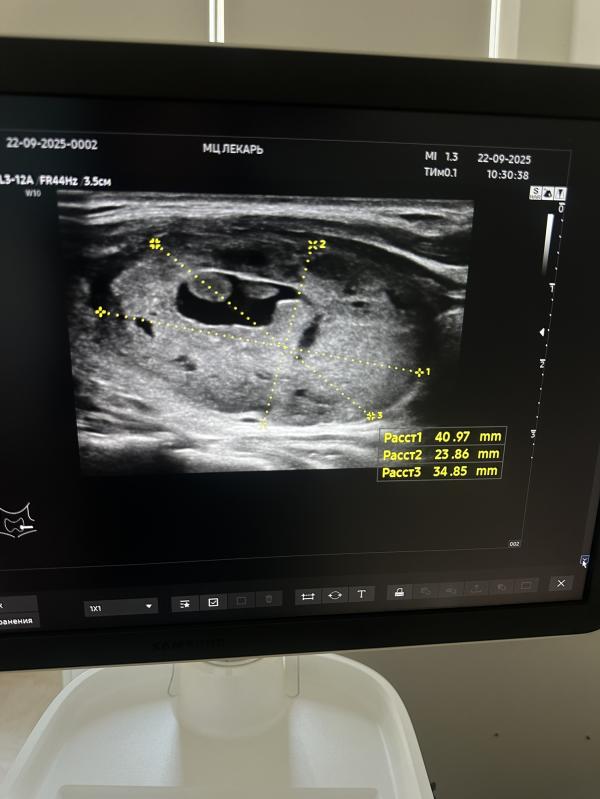

Обнаружение узла щитовидной железы 4 см на УЗИ в 38 недель

Предродовое УЗИ проводится в 38 недель

У данной беременной была жалоба на ком в горле, поставив датчик-большущий узел достигающий 4 см

Показано срочное ТАБ узла …